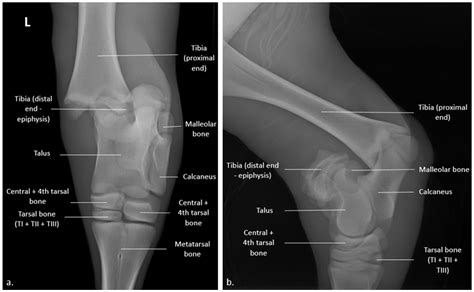

The growth plate, or physis, is a specialized area of cartilage found at the ends of long bones in children, such as the bones in the arms, legs, fingers, and toes. These plates are responsible for the longitudinal growth of the bone. Unlike mature bone, which is dense and rigid, the physis is soft and vulnerable to mechanical stress. Once a child reaches physical maturity, these plates harden into solid bone, meaning they no longer function as sites of growth. It is during this active growth phase that a Growth Plate Fracture is most likely to occur, often triggered by sports injuries, falls, or motor vehicle accidents.

• X-ray Imaging: The primary tool for diagnosis, though it is important to note that growth plates can be difficult to see on standard X-rays, often requiring comparisons to the uninjured limb.